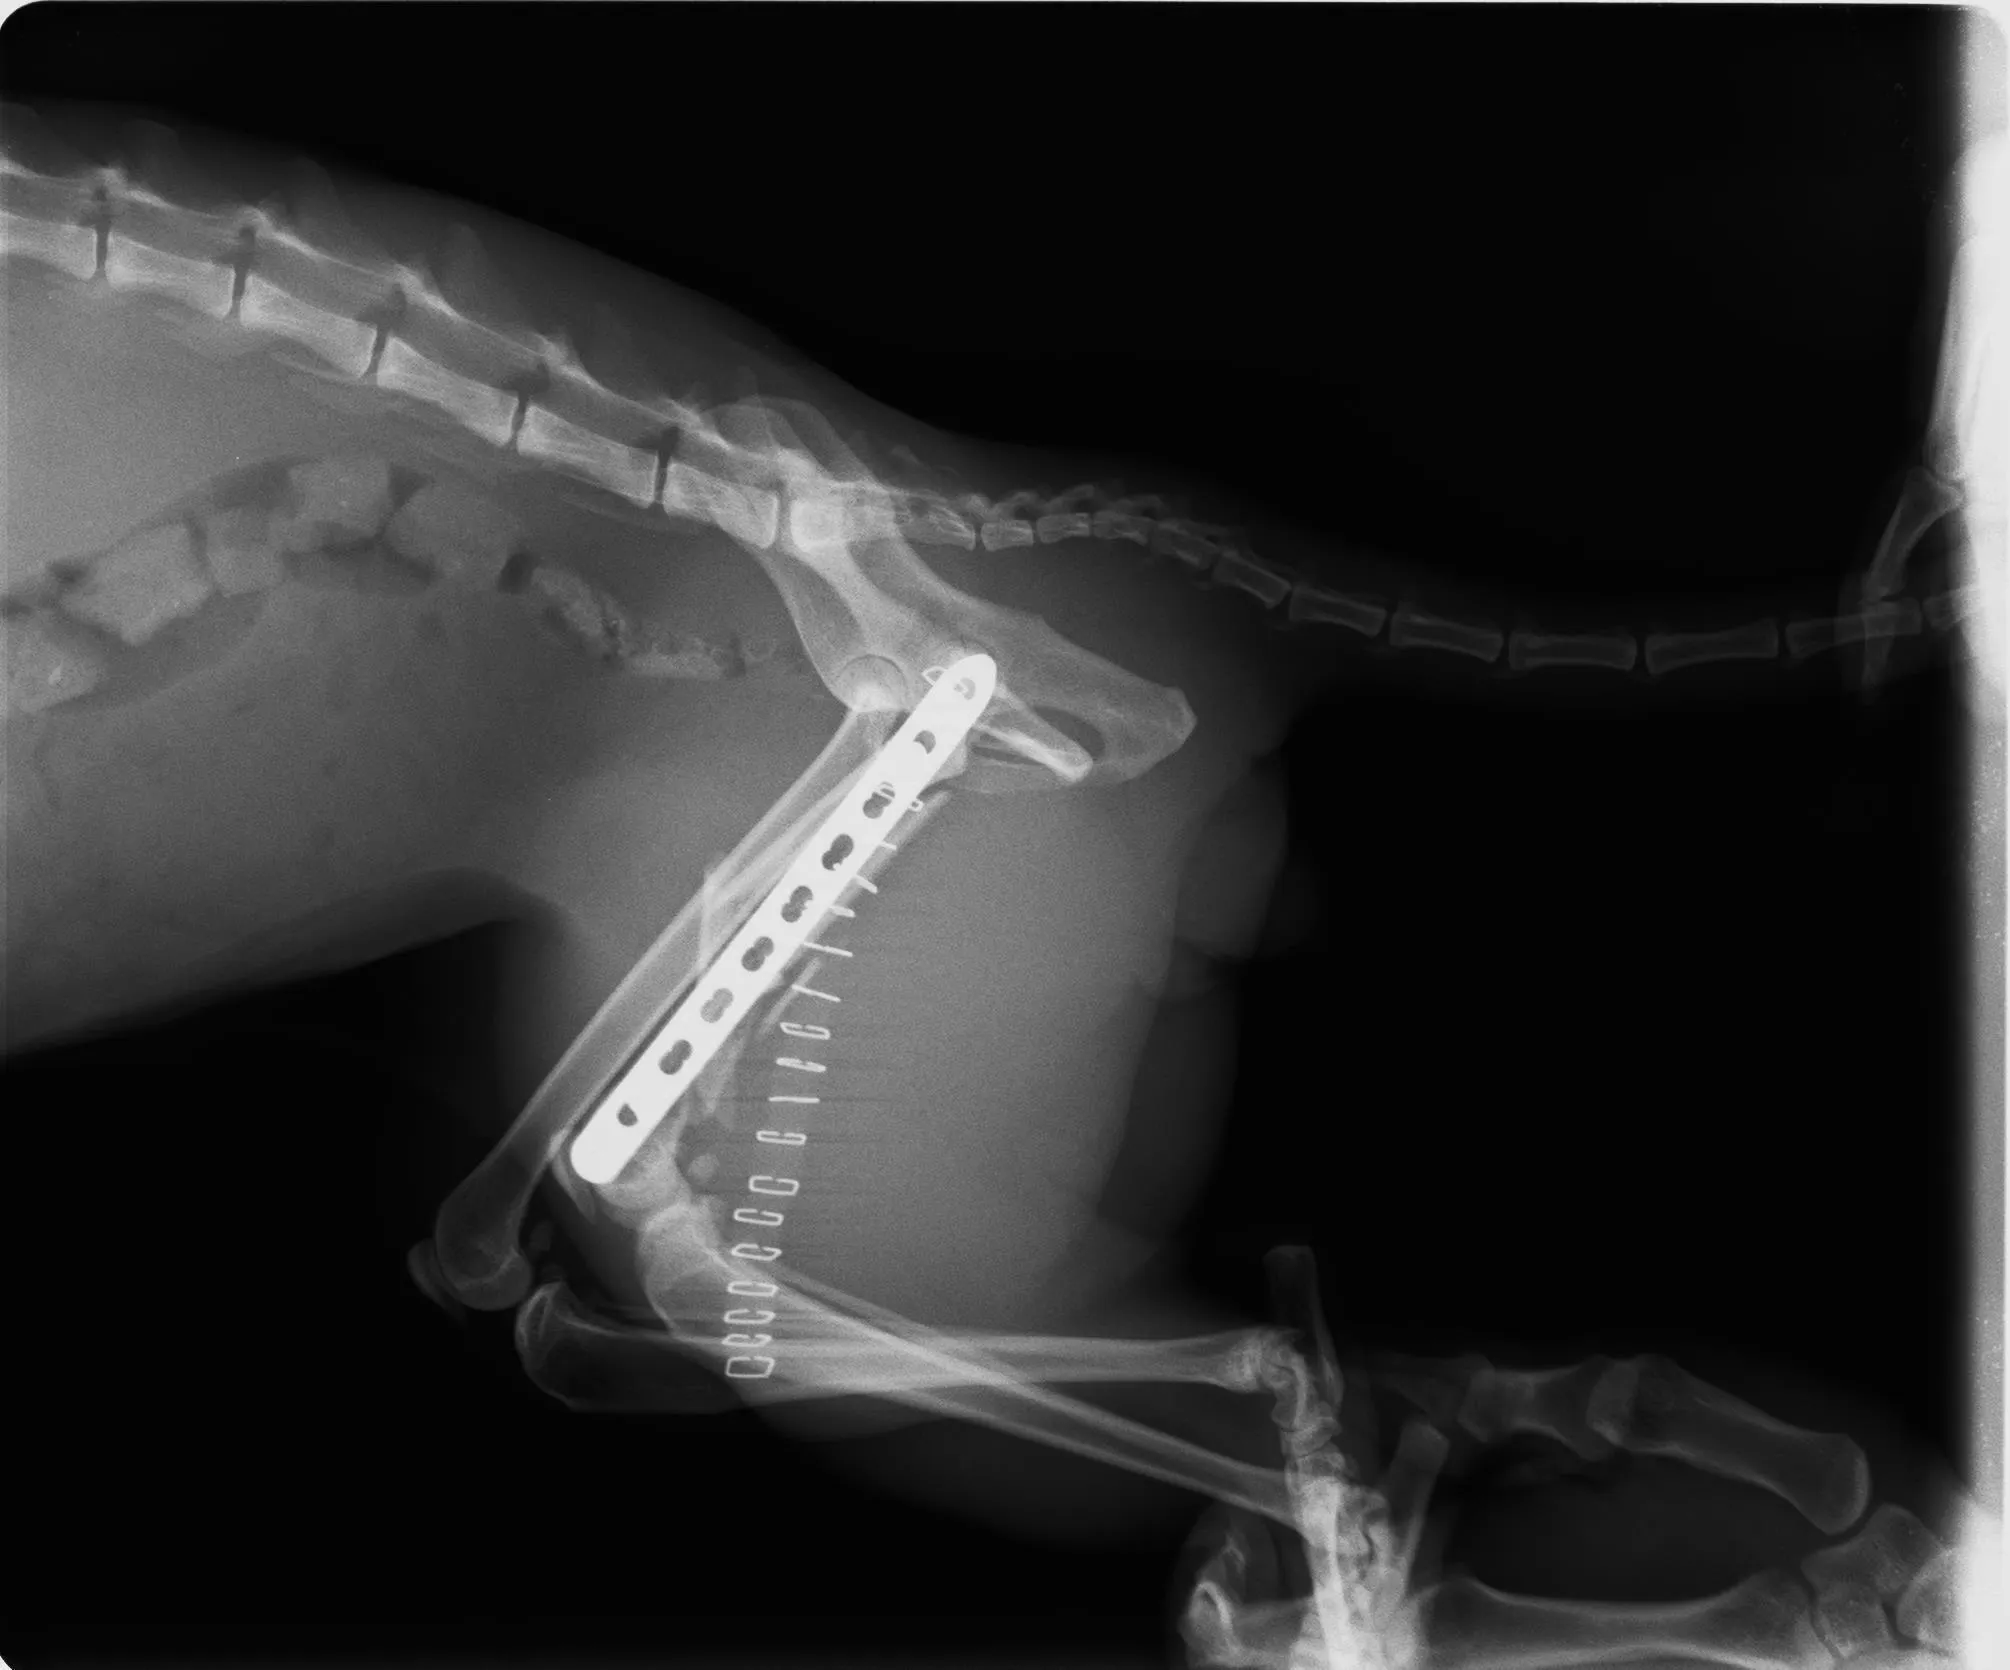

左側大腿骨はかなりひどい粉砕骨折だが、プレートを入れる手術を行い四足歩行できる状態を目指し、手術決行

7/20 手術は無事に成功

・左大腿骨複雑骨折 手術・入院費用(7/19〜21)

退院後の内服薬含む 382,140円

・退院後の整形外科通院費(3ヶ月分)

レントゲン、診察代 7,000円✕6回 42,000円